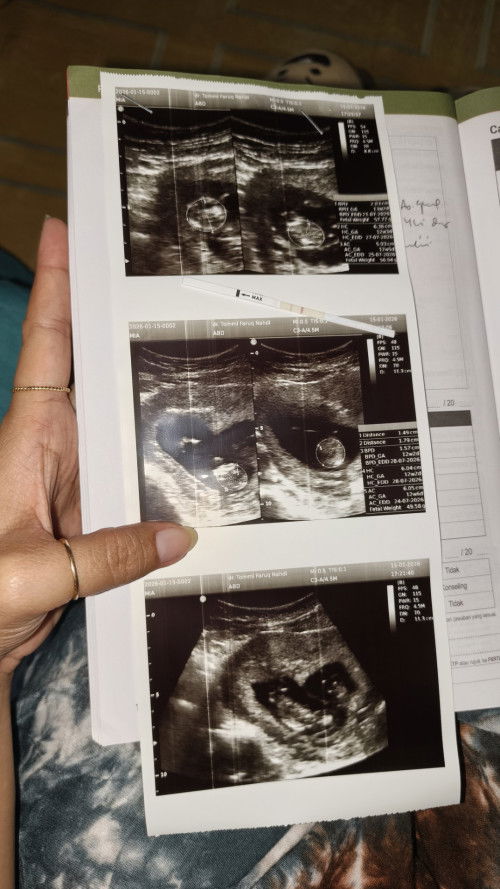

Aku bingung Bun, suami gak kerja udah hampir 2 bulan ini, aku punya anak 2, sekarang lagi hamil anak ke 3 hpl juli. Sementara keluarganya suami bener2 gak ada bantu sama sekali, selama ini kami hidup dari orang tua ku. Ya makan, jajan anak, sampai kami masih tinggal sama orang tua ku. Aku sama suami udah berusaha untuk mencari pekerjaan, tapi belum dapat. Sementara BPJS aja kami belum punya.😭😭 Gimana nanti aku mau lahiran, sedih aku kehidupan kaya gini Bun😭#Sharingdong_Bund #sharing